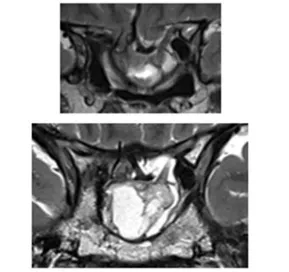

咨询到神经外科后,经过核磁共振检查后原来小葵脑子里长了一个垂体泌乳素瘤(图1)!小葵之所以会出现严重的视力下降,就是因为肿瘤已经压迫到了视神经,而随着肿瘤的持续增长,小葵很可能远远失去视力……

图1:初始病灶

8年逃不过复发“魔咒”,突发中风、继发空碟鞍综合征

图:影像显示一开始肿瘤切除8年后复发,并伴有脑出血和鞍底下陷

图2:术前MRI显示二次手术后肿瘤残余、患者出现继发性空蝶鞍综合征的影像学特征